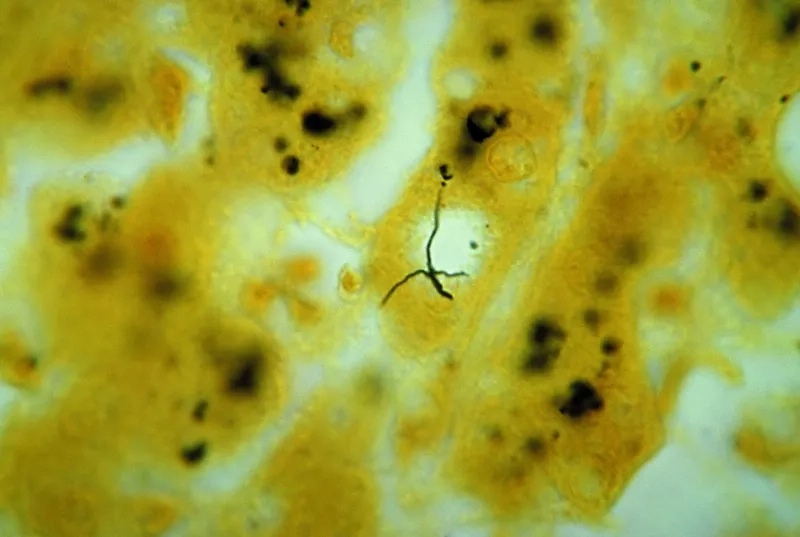

Image of the disease Leptospirosis